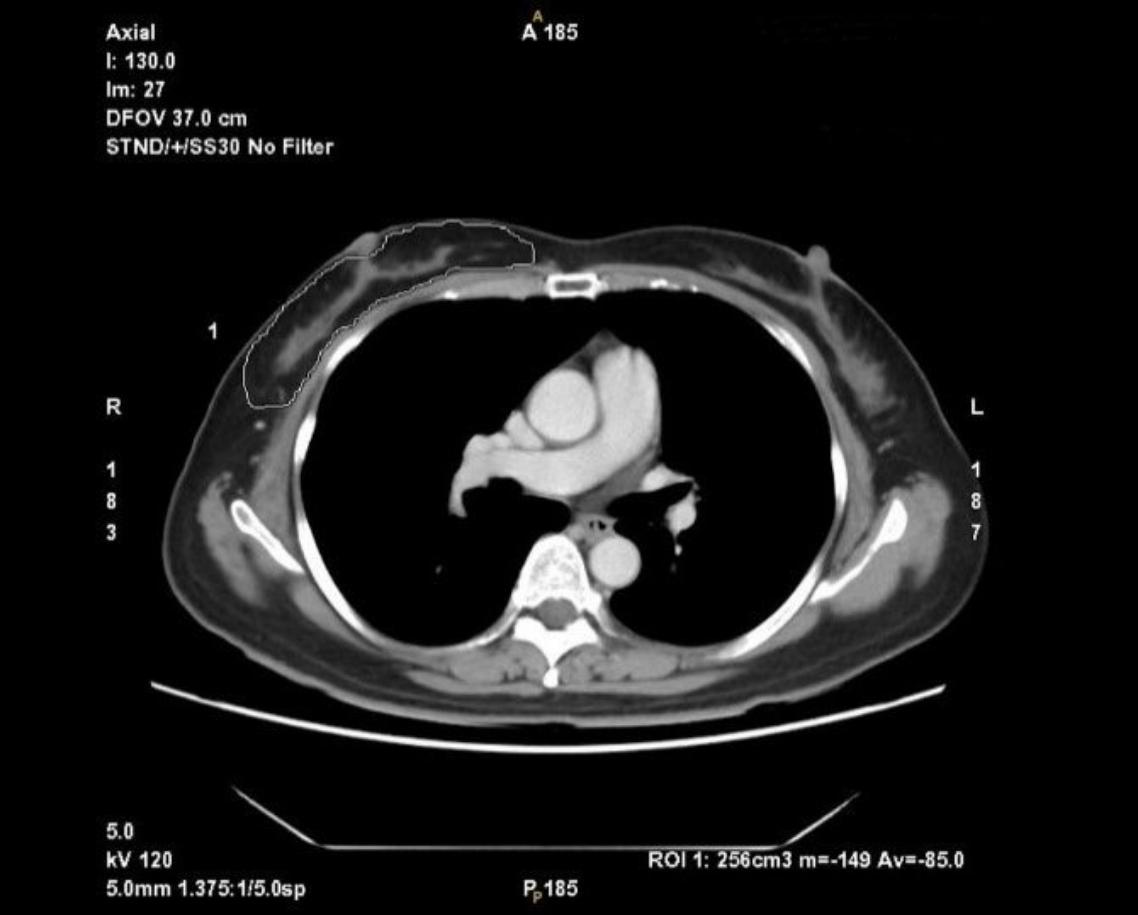

57歲的陳小姐,生活規律,向來健康,卻在今年健檢的乳房攝影,發現雙側乳房微鈣化,轉診基隆長庚做切片病理化驗,證實罹患乳腺管原位癌。由於病人希望治療的傷口小,且後續不要再接受輔助的放射線治療,因此基隆長庚醫療團隊運用先進的達文西手術進行乳房全切除,再以立即深下腹動脈穿通枝皮瓣完成立即性乳房重建。

目前雖有研究顯示,乳腺管原位癌對於範圍較小、沒有多象限多發性病灶,且切除後安全邊界可以達0.2公分以上者,可接受乳房保留手術加上術後放射線治療,其預後與全切除相近,但是陳小姐因為鈣化點太過廣泛,無法確認安全邊界及有無多發性病灶,所以建議做乳房全切除。

簡禔萱醫師表示,基隆長庚醫療團隊運用先進的達文西機器人手臂進行乳房全切除手術,具有傷口拉扯較小、乳頭部份乳管切除較清楚等優點,並且只有外側乳房約5公分切口,即可安全完成乳房全切除及前哨淋巴切片手術。